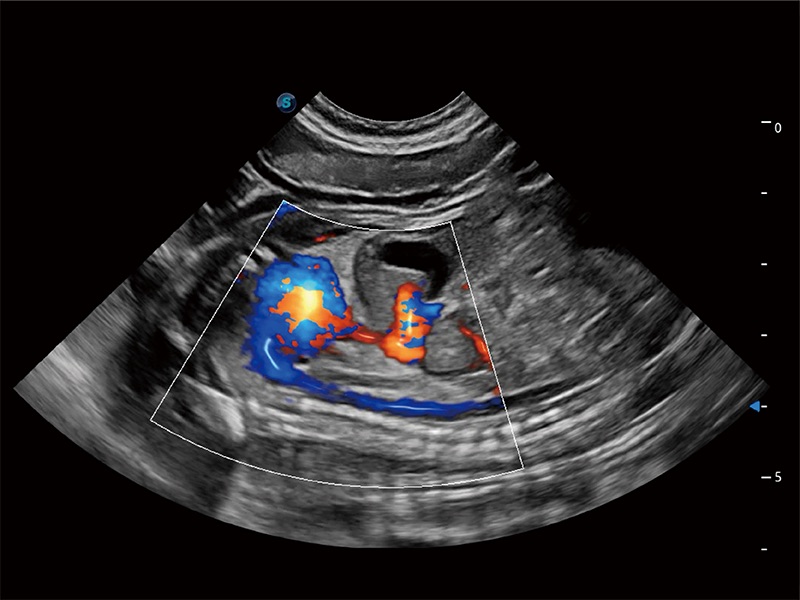

ProPet 80 配备了丰富的心脏探头群、先进的成像技术和专业的心脏测量工具,可帮助动物医生为不同体型和生理结构的动物提供心脏和心肌功能的全面评估。

通过心肌识别技术与二维斑点追踪技术相结合,对心脏的超声图像进行量化分析。计算心肌17个节段的应变、应变率、速度、位移等,并通过牛眼图的形式进行呈现。

通过360度任意调节3条M型取样线,在同一心动周期上观察心脏不同位置的运动曲线,得到准确的心功能测量数据,有效评估心肌运动及左心室功能。